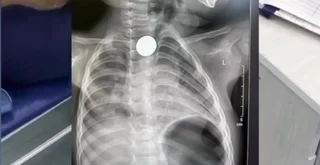

Бишкекте наристенин кызыл өңгөчүнө тыгылып калган тыйын операциясыз чыгарылды

08 Апрель 2026

15:10

1334

Ден соолук